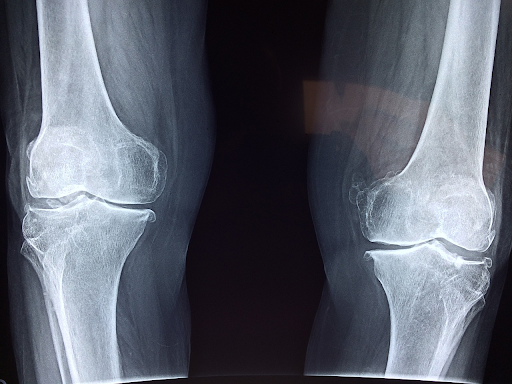

While the studies were conducted on postmenopausal women, it can be assumed that poor air quality will accelerate the rate of bone mineral density loss in men and premenopausal women too. Bone mineral density is simply a measurement of how many minerals are in your bones, which subsequently determines how strong the bones are. Simple tests facilitated by x-rays can give an accurate estimate and take less than 15 minutes to complete.

A person that scores 2.5 SD or more below the young adult mean will be classed as having osteoporosis while someone that is between 1.0 SD and 2.5 SD is considered to have a low bone mass that has not yet progressed to osteoporosis. When surrounded by poor air quality, the rate of progression from a low bone mass to osteoporosis is noticeably faster. Patients will also develop severe osteoporosis, which is when fractures occur, in a shorter time.